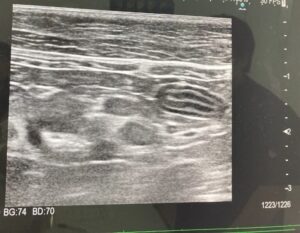

元保護猫あんこ・もなか 多頭飼いでぶねこシニア猫高齢猫 【シニア猫の体調記録】尿比重低め?肛門腺トラブル?もなかの経過と、回復までの記録 2026年1月7日 年明け早々、愛猫もなかの体調がやっぱり気になり、再び動物病院を受診しました。 嘔吐や下痢はないものの治らないお尻の脱毛、粘液のある便、そして尿検査で告げられた「尿比重がやや低め」という言葉。 腎臓の弱りかもしれないと言われ、薬とフードを切り替えながら経過を見守ることになりました。 この記事では、高齢猫もなかの通院内容と... lingo

元保護猫あんこ・もなか 多頭飼い嘔吐下痢便秘 シニア猫の嘔吐と下痢・しぶり便…腸管型リンパ腫?膀胱炎?動物病院に駆け込んだ話 2025年12月23日 今年6月、もなかが嘔吐や下痢(便秘?)の症状で急きょ病院へ駆け込んだできごとを書きました。実は最近、また同じような症状が出てしまい、今回は前よりも回復までに時間がかかっています。検査でははっきりした病名がつかず、不安な気持ちと向き合う日々。もしかしたら同じような症状で悩んでいる猫さん、飼い主さんがいるかもしれない。そん... lingo